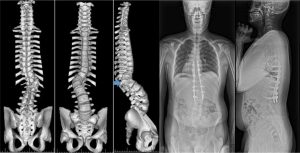

早期発症側弯症:10歳未満に発症するため、最初から固定はせずに年2回程度、矢印の所を延長する手術を成長が終了するまで続け、最後に固定術をします(growing-rod法)。

先天性側弯症:半椎とよばれる余剰椎(➡)により側弯や後弯が進行します。余剰椎を完全に取り除きます。